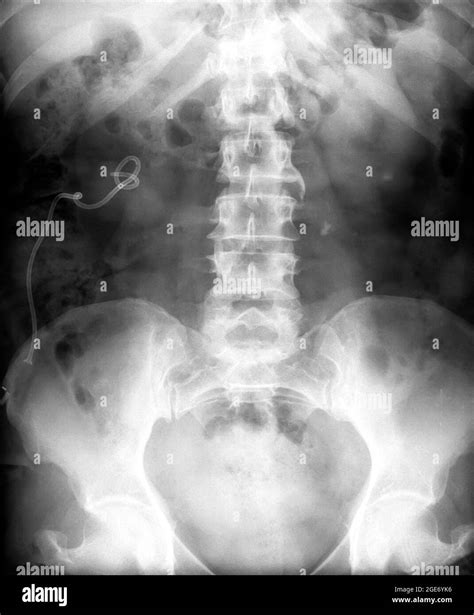

A Lower Back X Ray is a common, non-invasive imaging test that uses a small amount of radiation to create pictures of the lumbar spine. The lumbar spine consists of the five vertebrae in your lower back. By capturing these images, doctors can evaluate the bones, joints, and overall alignment of the lower spine.

Unlike more advanced imaging studies, such as an MRI or CT scan, a plain X-ray focuses primarily on dense structures like bone. While it cannot show soft tissues like nerves, discs, or muscles in great detail, it is highly effective for identifying bone-related problems that often cause chronic pain.

Undergoing a Lower Back X Ray is a straightforward and generally quick process. You will be asked to change into a hospital gown to ensure no metal objects, like zippers or jewelry, interfere with the image quality. You may be required to stand, sit, or lie down in different positions—such as on your side or back—so the technician can capture images from multiple angles. This ensures a comprehensive view of the lumbar region.

What Can Be Seen on a Lower Back X Ray?

While an X-ray has limitations, it is excellent at highlighting specific issues. The following table summarizes what clinicians look for when reviewing these images:

Condition What the X-Ray Shows

Fractures Disruption or cracks in the vertebrae bone.

Arthritis Narrowed joint spaces or bone spurs (osteophytes).

Scoliosis Abnormal side-to-side curvature of the spine.

Spondylolisthesis One vertebra slipping forward over the one below it.

Infections/Tumors Areas of bone destruction or abnormal bone growth.